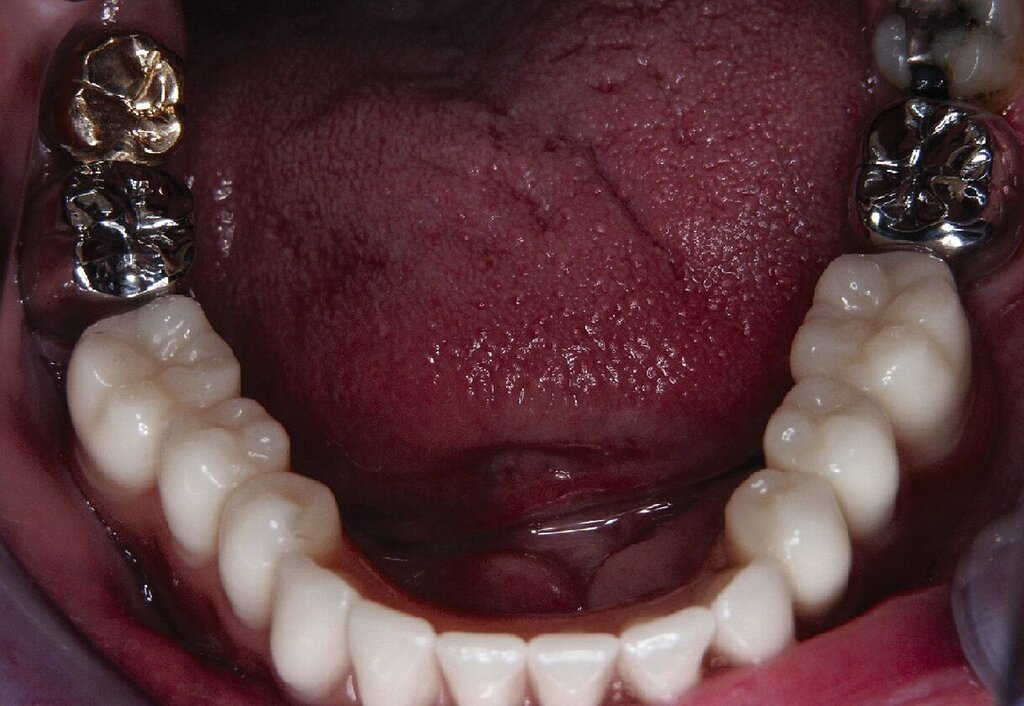

Eine präoperativ vorbereitete Interimsprothese, die über zwei gegossene Bonwill-Klammern sowie das verbliebene Implantat in regio 35 stabil abgestützt war, diente gleichzeitig als Verbandsplatte (Abb. 1f). Auf eine Glättung scharfer Knochenkanten oder die Nivellierung der Kieferkämme wurde verzichtet, um einen iatrogenen Knochenverlust zu vermeiden und das regenerative Potenzial des verbliebenen Knochens zu nutzen (Abb. 1g). Bereits bei der röntgenologischen Kontrolle nach drei Monaten war eine deutliche Zunahme des Knochens im Bereich der alten Implantatpositionen zu erkennen (Abb. 1h). Eine Nachimplantation von vier Implantaten in den Positionen 32, 34, 42 und 44 erfolgte neun Monate nach der Explantation und einer vorangegangenen Verbesserung der Weichgewebsbedeckung durch multiple freie Schleimhautransplantate vom harten Gaumen. Die knöcherne Regeneration unter der gut abgestützten Modellgussprothese verlief so günstig, dass sich der vertikale Höhenverlust des Alveolarkamms im Bereich der gescheiterten Implantate auf circa 2 mm begrenzen ließ. Das zur Entlastung der Kieferkämme und der einheilenden Implantate außerordentlich hilfreiche Implantat in regio 35 wurde erst nach dem Einheilen der nachgesetzten Implantate entfernt. Nach der Einheilzeit der Implantate von weiteren drei Monaten wurde eine kombiniert Zahn/Implantat-gestützte Teleskopprothese mit intraoral verklebten Galvano-Sekundärkronen eingegliedert (Abb. 1k bis 1m). Inzwischen ist diese, wie eine herausnehmbare Brücke abgestützte UK-Prothese seit zehn Jahren funktionstüchtig ohne Zeichen einer Periimplantitis an den vier Implantaten.